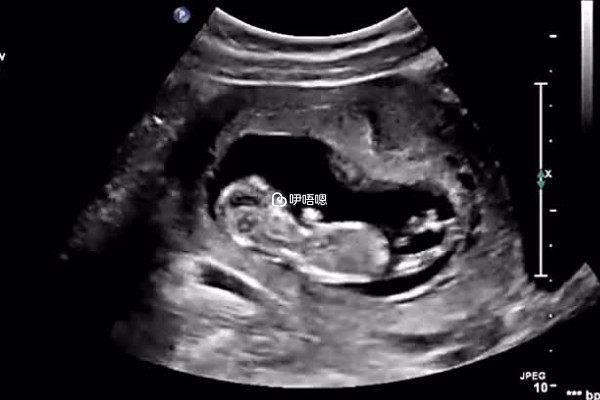

胎芽是指在受精卵發育過程中,最初兩週稱為孕卵,一般孕6-7周B超可見胎芽,以後各種器官逐漸形成,在孕8周以前的胚胎,妊娠三至妊娠第一個月四周稱為胎芽期,以下則是民間流傳的看男女的方法,僅供參考:

- 1. 網友傳言如果胎芽的最長徑在13-18毫米之間,像茄子或者是呈長條狀的話是男寶寶的可能性大,如果圓鼓鼓像球一樣的話,是女寶寶可能性大;

- 2. 如果胎芽大小的長和寬的相差在一倍以上,那麼男寶寶可能性大,長和寬相等,或者相差不大的話,很可能是個女寶寶;

- 3. B超檢查是會獲取3個數據,如果兩個資料差不多,第三個資料比前兩個小一倍,就是是兒子,如果成遞減資料就是女兒;

- 4. 還有一種說法這餓是如果胚芽出現的早,就有可能生兒子,如果出現的晚一些則就有可能生的是女兒。